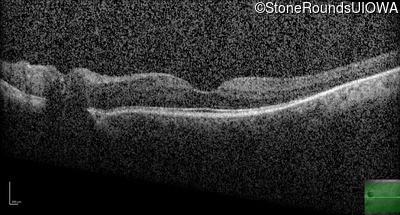

Optical Coherence Tomography - Left - 20/25

Exemplar / OCT Stack